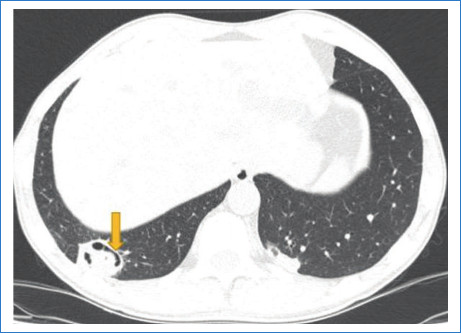

El signo del menisco pulmonar también se ha descrito como el signo del aire creciente o el signo de media luna. Corresponde a una colección de aire en forma de luna creciente que se visualiza en la radiografía y en la tomografía de tórax como una radiolucencia dentro de un área de consolidación o un nódulo; puede variar de forma, de media luna hasta encapsular totalmente la lesión (Fig. 1). Este signo radiológico, que no es patognomónico de aspergilosis, fue descripto en el año 1975 inicialmente por Bard y Hassani, quienes explicaron en un hematoma pulmonar el signo de la media luna, y en 1979 Curtis describió este signo como una forma invasiva de aspergilosis1.

Aspergillus es un hongo filamentoso conformado por cadenas celulares llamadas hifas. Fisiopatológicamente, estas alteran las paredes de los vasos sanguíneos a través de las arterias bronquiales generando oclusión de la luz vascular, lo que lleva a la necrosis y cavitación. Esto se refleja radiológicamente como un área de vidrio esmerilado, consolidación y/o nódulos peribronquiales. En su evolución el centro infartado se retrae y se reabsorbe, resultado de la reacción neutrofílica, dejando un área de tejido desvitalizado que se desprende del resto de la consolidación2. El aire que se encuentra entre el tejido desvitalizado y el parénquima consolidado que lo rodea tiene forma de media luna o del aire creciente (Fig. 2). Este signo es tardío, coincide con una recuperación progresiva de la infección y depende de la función leucocitaria, por lo cual generalmente se observa en pacientes inmunocomprometidos, que en general inician clínicamente con cuadro de hemoptisis3.